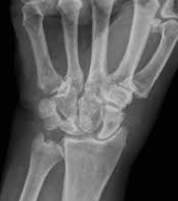

대부분 근골격계 통증이 일시적이지 않고 3개월 이상 지속하는

경우와 통증의 부위가 18개 중 11개 이상인 경우 섬유근육통의

가능성이 매우 높다고 판단한다고 하네요.

근골격계 및 신경계 검사에서 이상이 없기 때문에 이 역시

의사마다 진단 기준이 조금씩은 다를 수 있다고 합니다.